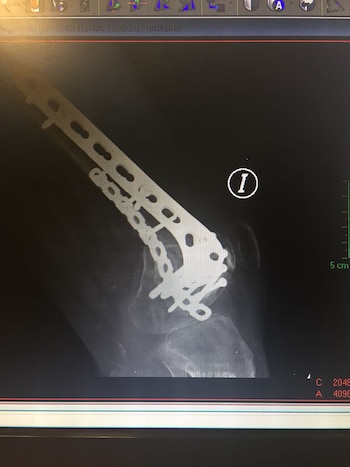

"Había sufrido múltiples fracturas en el fémur, que es algo rarísimo. Y también sufrí una luxación de la rodilla, eso significa que todos los cartílagos, ligamentos y meñiscos se desprendieron. El golpe fue justo entre el fémur y la rodilla".

"Me pusieron un total de 24 clavos, ocho de ellos solo en la rodilla. Con el hueso no hay drama porque se regenera, pero los cartílagos no. Entonces hasta el día de hoy, cuando camino, se me choca hueso con hueso, y eso representa un dolor inimaginable", aseguró.

En menos de 24 meses, Eliana debió someterse a cuatro operaciones en su pierna. Así, se inició una vida habituada a los períodos postoperatorios prolongados y sesiones de dos horas diarias de fisioterapia ininterrumpidas durante más de un año y medio.